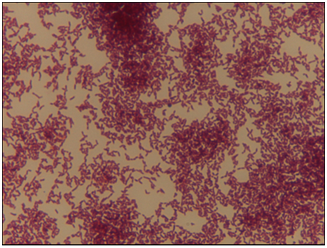

It was performed fine-needle aspiration puncture (FNA) in the subcutaneous nodule of the left knee and right elbow. It was obtained an hemato-purulent liquid without foul odor. A day later, oozing skin fistula appeared in his right knee. Histopathological examination of pus of knee and elbow subcutaneous nodules showed, abundant inflammatory infiltrate with eosinophil and polymorfonuclear neutrophils, and eosinophilic filamentous accumulation suggestive of Actinomyces (Figure 1). No neoplastic cells were obtained. Taking into consideration the results, treatment was switched to intravenous Penicillin G (5million units/6hours). Pus samples of subcutaneous nodules were incubated in anaerobic conditions in chocolate blood agar media. Cultures were positive at tenth day, filamentous Gram-positive fungal-like pathogens (Figure 2). Identifying species of Actinomyces meyeri was made by matrix-assisted laser desorption ionization time-of-flight (MALDI-TOF). It was sensitive to amoxicillin, penicillin, clindamycin, piperacillin-tazobactam and meropenem, and resistent to metronidazole.

Figure 1 Sulfur granules of Actinomyces (H&E, x20).

When there is a mucosal barrier disruption, microorganism invades the soft tissues without respecting anatomical plans.11 Hematogenous dissemination can occur from the common primary sites and is reported in 3% of cases.17 Lymphatic spread is uncommon.2,12,14,17 Typical microscopic findings include necrosis with yellowish sulfur granules and filamentous Gram-positive fungal-like pathogens.7 Sulfur granules is seen only in 25% cases.5 Usually, histological study is more sensitive than culture.7 Cultures are negative in more than 50% of cases.7 It is explained because of previous antibiotic therapy, inhibition of Actinomyces spp growth by concomitant microorganisms, inadequate culture conditions, inadequate-short-term incubation, or overgrowth by bystander organisms.7,13,18 The growth usually appears within 5 to 7days, but primary isolation may take up to 2 to 4weeks.17